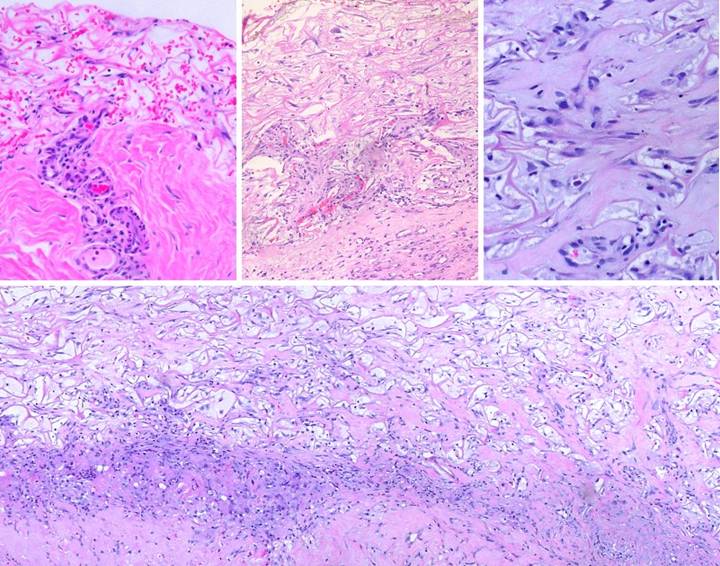

Case Study 12,  Location, leg.   A 77 year old woman had a 40 year history of continuous leg ulceration and progressive systemic illness.  In spite of classic symptoms of Sjögren’s disease, the diagnosis was missed countless times.  When seen in consultation, the diagnosis was made, anti-inflammatory and antimetabolic treatments were started, and the patient’s general health status improved substantially.  (Figures 12a,b)  The leg ulcers are shown just prior to excision.  Proper excision means thorough fasciectomy, removing all pathological tissues, including the fibrotic, ulcerated, and inflamed sural fascia.  This means that muscles, tendons, retinacular ligaments and other structures will all be exposed when excision is complete.  Skin grafts will not cover these structures, and even if they could in principle, here they would be at risk for recurrent pathological lysis and ulceration.  (Figures 12c,d)  The legs and ankles are shown one week after excision and Integra.  Note the wrinkling in the Integra, a common occurrence due to control of  inflammation and edema, thereby decreasing limb volume and surface.  All care was outpatient.  (Figures 12e,f)  The legs healed and have stayed stable, shown here two years later.  Note the bandaging imprints, attesting to the patient’s diligent efforts to control edema and care for her skin.  Consistent rheumatology management has kept the patient healthy, and lifestyle has been restored.  (Figure 12g)  A close-up view shows the quality and texture of the regenerated material and how comparable it is to normal skin.

Figure 12  a, b (left column), c, d (middle column), e, f (right column), g (bottom)